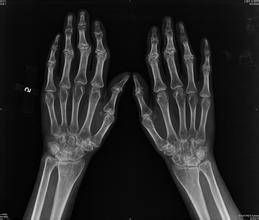

强直性脊柱炎是是一种已经存在很久的疾病,长期以来不断的有强直性脊柱炎患者在和疾病作斗争,目前,对于强直性脊柱炎的病因还没有完全明确,但研究发现但基因遗传和感染是导致强直性脊柱炎的肯定因素,下面为大家综述导致强直性脊柱炎常见的三大原因。